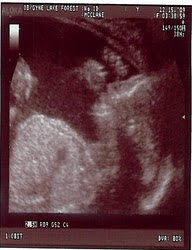

Here’s my first picture of my granddaughter to share with you! Anne’s April 29 due date is fast approaching.

What a sweet picture! Looks like she might be sucking her thumb. 🙂